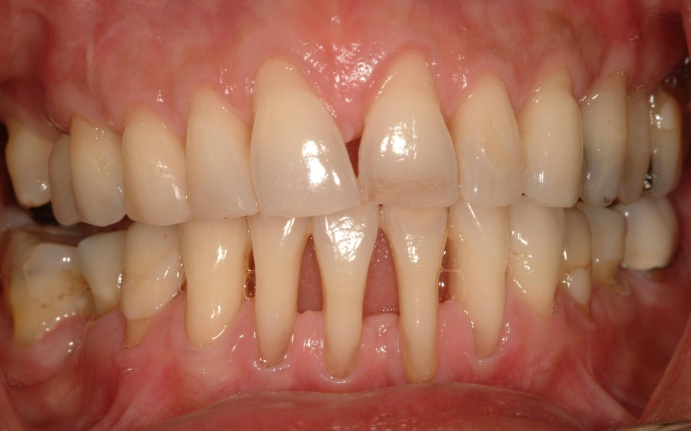

Patient with advanced periodontitis showing severe loss of bone and gum recession.